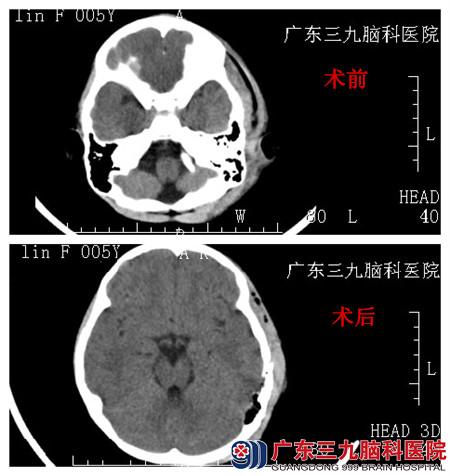

查体:患儿神志清楚,脸上多处皮肤擦破,已涂红汞;额部和左耳部位有肿胀,压痛明显,左外耳道可见少量淡红色液体。头颅CT示:左侧颞顶骨粉碎性凹陷骨折,脑挫裂伤,少量蛛网膜下腔出血。入院完善相关检查,小儿神经外科在全麻下行“粉碎性凹陷骨折整复术”,术程顺利,术中颅骨整复达解剖复位。术后予以预防感染、抗癫痫等综合治疗。经过13天的住院治疗,小霖康复出院。